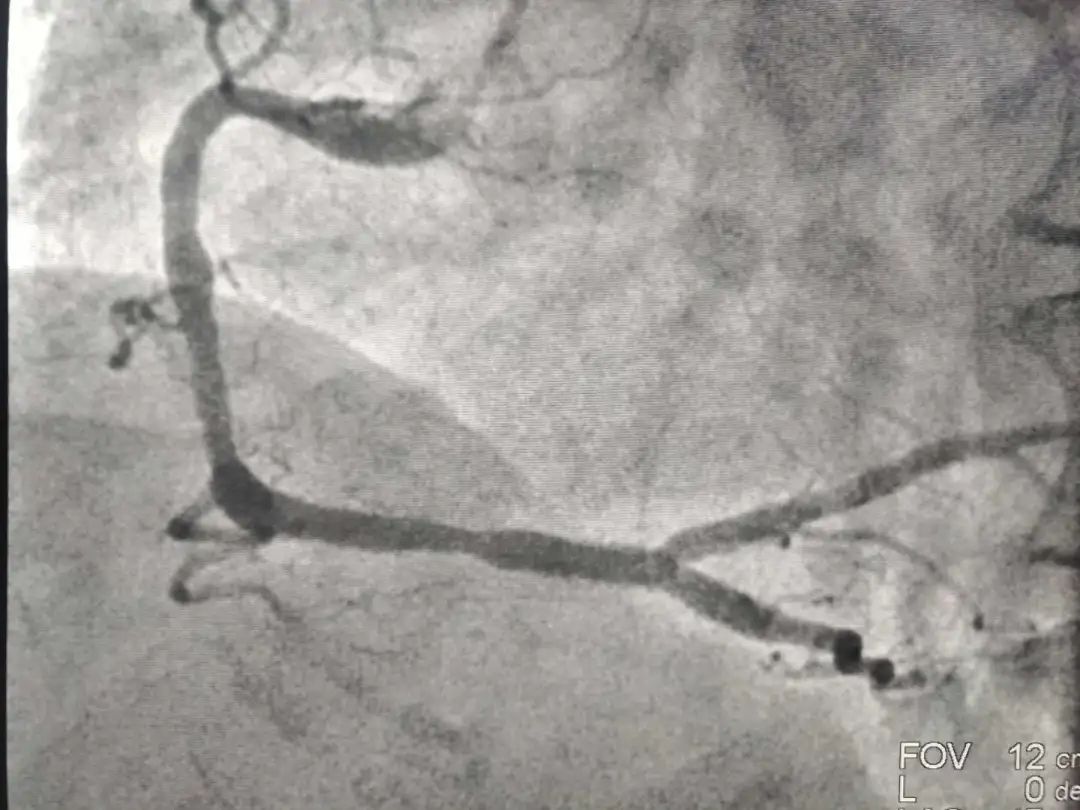

下午4点马先生被直接送至导管室,赶紧造影,发现右侧血管完全闭塞,左侧两个血管也有不同程度狭窄。我们第一时间打通血管,患者得到了救治,目前病情已经平稳。回到监护室,家属问我们,老马好好的,怎么就心梗了。老马不抽烟、没有糖尿病、饮食上也算注意,不太吃油腻的食物,偶尔还活动活动。有点高血压,但吃着药,我们平时每天还喝红酒来软化血管,怎么就心梗了?

术后